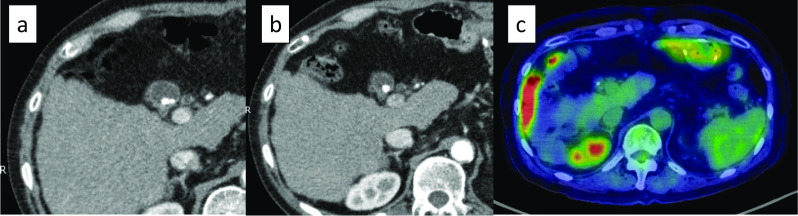

Case presentation: A 67-year-old man underwent a follow-up upper endoscopy 18 months after a partial gastrectomy for gastric cancer; an ulcerative lesion was found in the remnant stomach at the gastrojejunal anastomosis. A biopsy revealed gastric signet-ring cell carcinoma (SRCC). A full-body examination revealed no abnormalities other than gallstones in the gallbladder. With a diagnosis of residual gastric cancer (cT2N0M0 cStage I), the patient underwent open total gastrectomy and cholecystectomy. Macroscopic findings of the resected specimen revealed thickening of the gallbladder wall; however, no obvious neoplastic lesions were found on the mucosal surface of the gallbladder. The pathological findings showed that the SRCC had invaded the submucosa of the gastrojejunostomy site with a high degree of lymphatic invasion and lymph node metastases. SRCCs were also found in the lymphatic vessels of the gallbladder wall. These findings suggested the possibility of gallbladder metastasis through lymphatic vessels. The patient and his family members refused postoperative chemotherapy. Ten months after the operation, the patient experienced respiratory failure due to lymphangitis carcinomatosa and died.